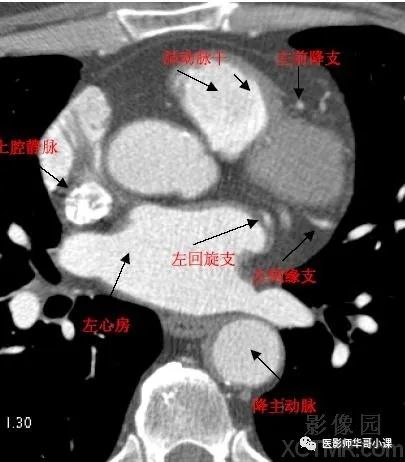

影像解剖 | 心脏冠状动脉ct解剖中文详细标注(图文)